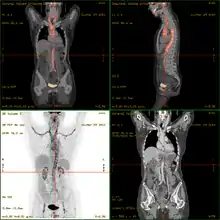

- 18F-fluorodeoxyglucose positron emission tomography/computed tomography (FDG-PET/CT)has become a widely used imaging tool in patients with suspected Large Vessel Vasculitis, due to the enhanced glucose metabolism of inflamed vessel walls.[15] The combined evaluation of the intensity and the extension of FDG vessel uptake at diagnosis can predict the clinical course of the disease, separating patients with favourable or complicated progress.[16]